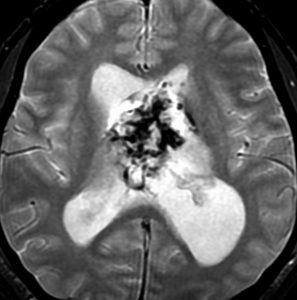

巨大な上衣下腫,でも良性のもの

52歳の男性で,2008年に脳ドックで見つかって無症状でした。中枢性神経細胞種 central neurocytomaを疑いましたが,上衣下腫 subependymomaはまったく考慮に入れませんでした。壮年男性でしたから経過観察しました。右側は2019年,11年後のものです。徐々に増大して水頭症になり歩行障害がでてきました。

手術前の画像です。血管が豊富で大きな導出静脈がみられ,腫瘍内出血もあります。ガドリニウムでは部分的に増強されます。CISS/FIESTAの画像では,透明中核から発生したようにみえて,脳浸潤は全くありません。脳弓は腫瘍の底面にありますが,もちろん境界はっきりしません。これらもcentral neurocytomaの画像所見として捉えられるものです。

transcallosal approach 経脳梁法で亜然摘出しました。底面には脳弓があって剥離できないから全摘出はできません。病理所見は,のう胞形成を伴う線維性基質の中に楕円形の細胞が索状または小巣状に増生するものでsubependymomaと診断されました。異型は軽度で,核分裂像はなく,MIB-1染色率は1%以下のWHO grade Iの所見。EMAは細胞質にdot likeに陽性でしたがわずかであり,ependymomaとの合併腫瘍の診断には至りませんでした。